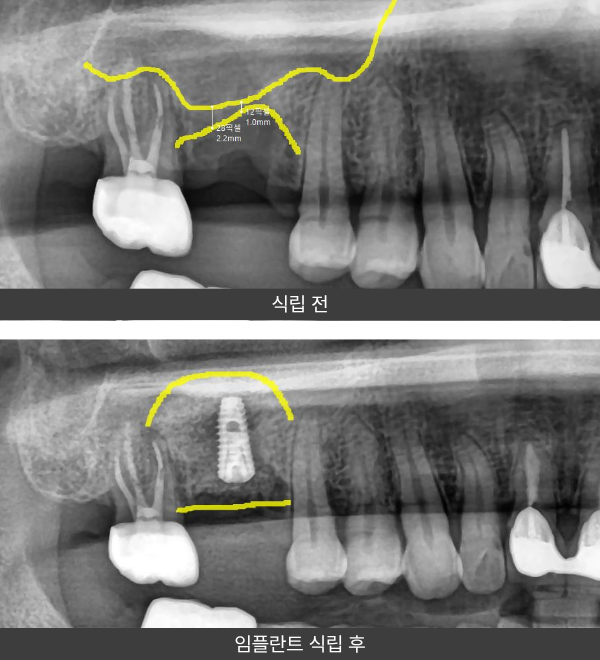

상악동거상술 임플란트

사례 1

“상악 어금니 부위 잔존골이 1mm 내외로

매우 부족한 상태였습니다.”

상악 어금니 부위의 잔존골이 1mm 정도로 얇게 남아 있어

임플란트 식립이 어려운 상황이었습니다. 상악동 거상술을 통해

상악동 막을 안정적으로 거상한 후 충분한 골 이식을 진행하고,

확보된 골 높이를 바탕으로 임플란트를 식립하였습니다.

환자 분께서는 타 치과에서 뼈가 부족하다는 이유로 치료가 어렵다는

설명을 듣고 내원하신 경우였으며, 수술 전에는 치료 가능 여부에 대해

많은 걱정을 하셨습니다.

상악동 거상술과 골 이식을 통해

식립 환경을 확보한 뒤 임플란트를 진행하였고,

현재는 기능적으로 안정적인 상태를 유지하며

일상적인 식사가 가능한 상태로 만족도를 보이고 계십니다.